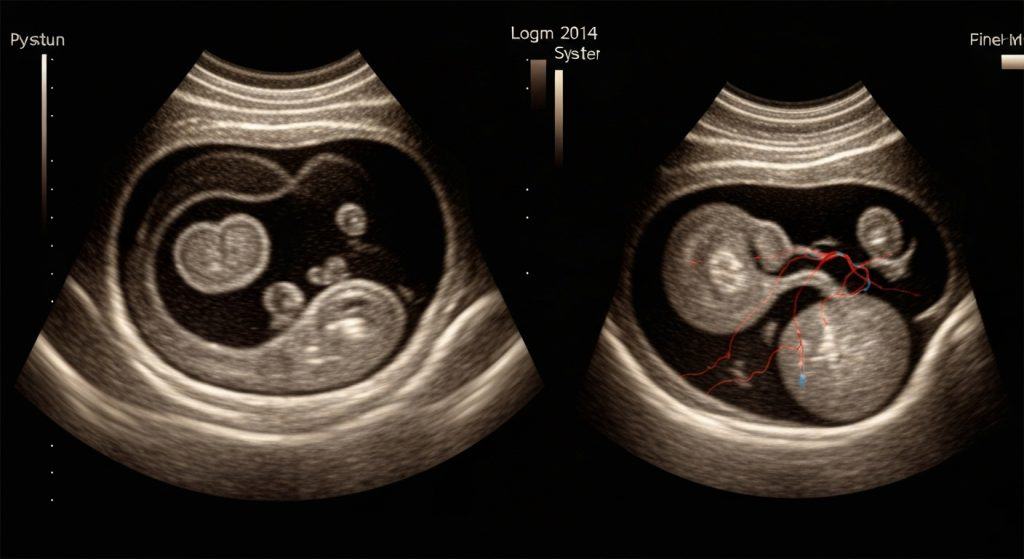

ד"ר אורי ארליך – המדריך המקצועי לסקירות מערכות בהיריון שכל אמא צריכה לקרוא

סקירת מערכות בהיריון: תהליך אולטרה סאונד מדויק לבדיקת התפתחות העובר. ד"ר אורי ארליך מאפשר פרטים לא נגישים. סוגי סקירות, זמנים ומה בודקים בכל ביקור, וכיצד להתכונן.